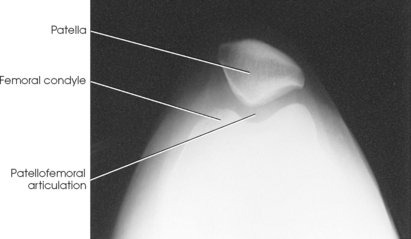

Structures shown: The image shows vertical fractures of bone and the articulating surfaces of the patellofemoral articulation (Figs. 6-162 and 6-163).